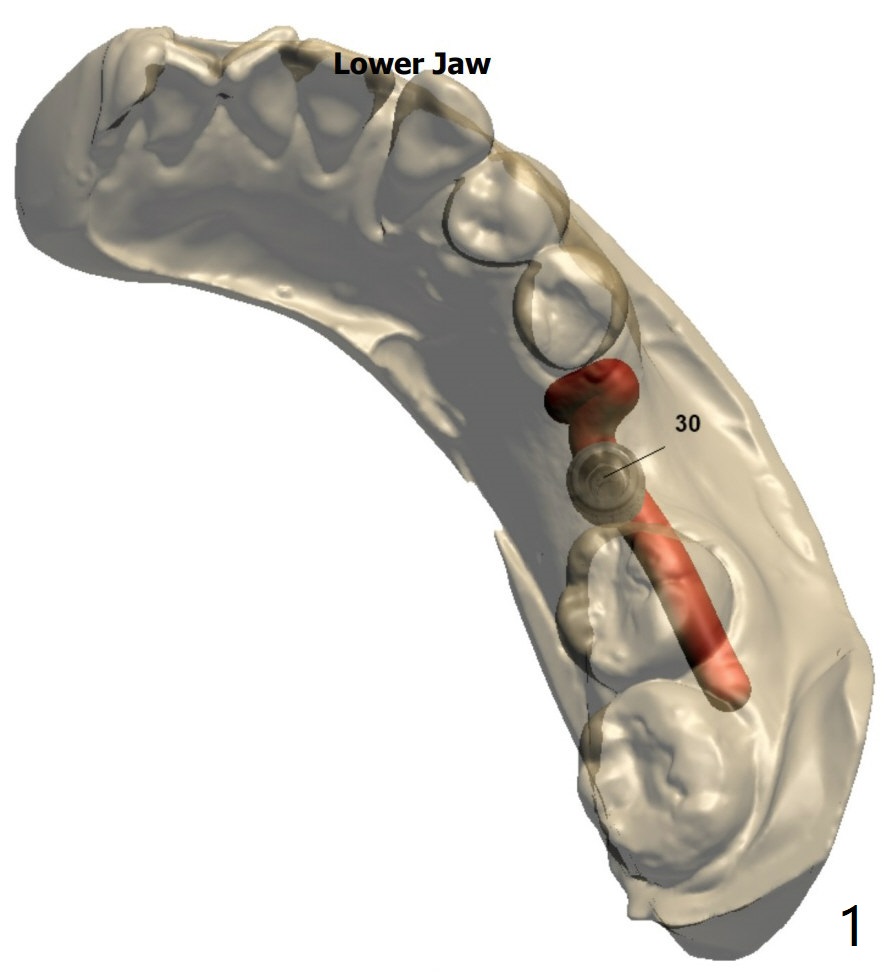

Extraction With No Bone Graft

A 45-year-old woman with #30 missing (~ 4 years, extraction without bone graft) requests treatment.